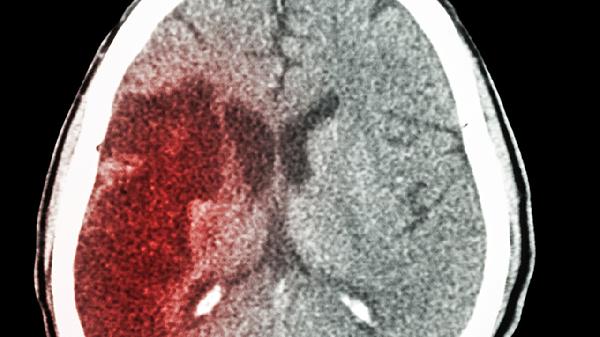

脑出血恢复期发烧可能与感染、中枢性发热、药物反应、深静脉血栓形成或吸收热等因素有关。脑出血患者可通过抗感染治疗、物理降温、调整用药、预防血栓形成或对症处理等方式缓解症状。

脑出血直接损伤下丘脑体温调节中枢会导致中枢性发热,体温往往超过39摄氏度且对退烧药反应差。患者可能伴有意识障碍、多汗等症状。可采用冰毯物理降温,必要时遵医嘱使用布洛芬混悬液等药物,需密切监测生命体征。